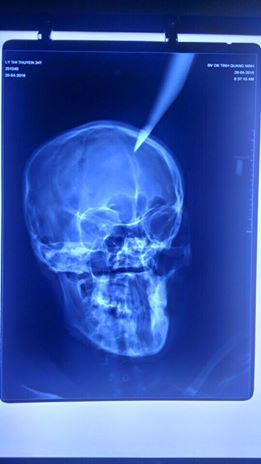

Thai phụ được đưa đến bệnh viện với con dao nhọn cắm sâu 4 cm vào đỉnh đầu

Kết quả chụp X-quang cho thấy phần đầu nhọn của dao cắm sâu 4 cm vào não. Theo người nhà bệnh nhân, vụ tai nạn hi hữu xảy ra khi bố chồng của chị T. sửa mái nhà đã vô tình làm rơi con dao dắt trong người xuống, cắm thẳng vào đầu con dâu đang đi qua ở phía dưới.